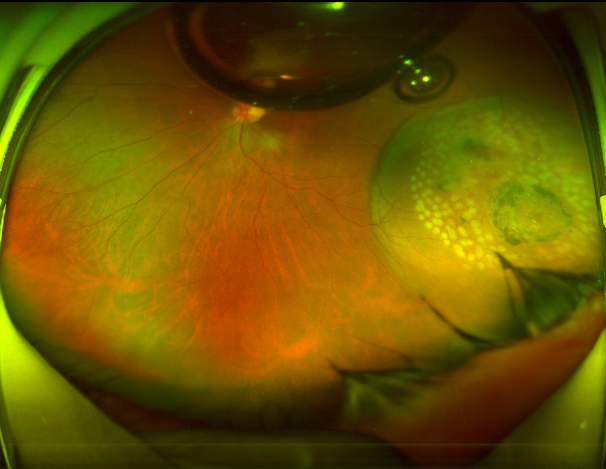

陈教授与Z女士就她目前的情况作了详细的说明和沟通。最后决定为其实施折叠顶压球囊(FCB)外路手术复位视网膜。手术当天,陈教授凭借丰富的经验、高超的技术成功地为患者实施了外路手术,使她的视网膜在术后顺利复位。